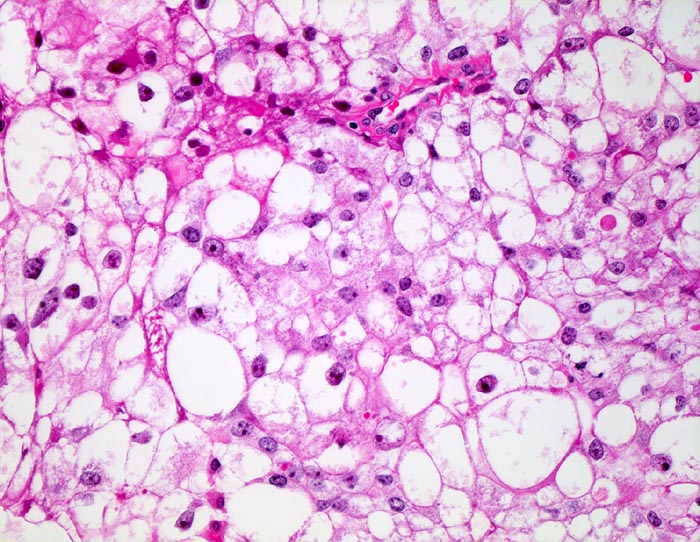

mässig differenziertes hellzelliges Nierenzellkarzinom

Tumorzellen mit deutlichen Zellgrenzen. Das reichlich vorhandene Zytoplasma ist entweder klar oder fein granulär eosinophil. Die Zellkerne sind polymorph, deutlich grösser als Zellkerne eines Nierentubulus und enthalten schon bei schwacher Vergrösserung gut erkennbare Nukleolen entsprechend einem mässig differenzierten Karzinom.

Beim hellzelligen Nierenzellkarzinom erfolgt die Gradierung entsprechend der Kernmorphologie. Die meisten Karzinome fallen in die Kategorie der mässig differenzierten G2 Tumoren. Hoch differenzierte G1 Tumoren haben kleine runde Kerne mit feinen Nukleolen. Mitosen sind kaum nachweisbar. Bei wenig differenzierten G3 Karzinomen lassen sich neben stark vergrösserten hyperchromatischen Kernen mit stark vergrösserten Nukleolen auch mehrkernige Zellen nachweisen.